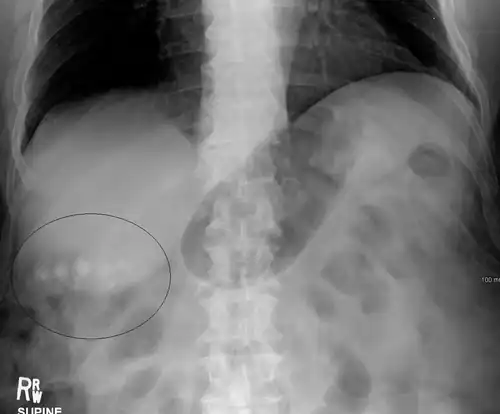

Biliary sludge and gallstones. There is borderline thickening of the gallbladder wall. - Gallstones as seen on plain X-ray